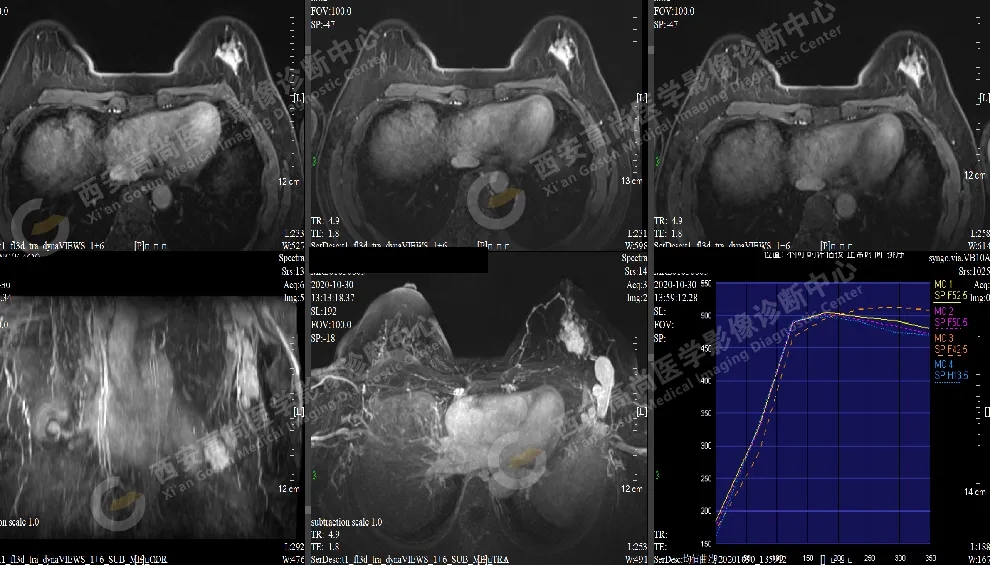

【病例二】女,46歲,左側(cè)乳腺5點方向乳腺Ca(BI-RADS IV-V級),左側(cè)腋窩多發(fā)腫大淋巴結(jié)轉(zhuǎn)移。